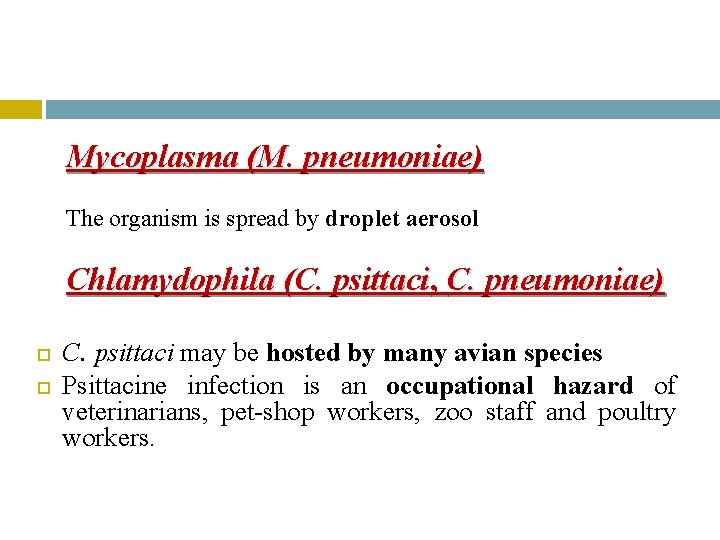

Mycoplasma (M. pneumoniae) The organism is spread by droplet aerosol Chlamydophila (C. psittaci, C. pneumoniae) C. psittaci may be hosted by many avian species Psittacine infection is an occupational hazard of veterinarians, pet-shop workers, zoo staff and poultry workers.